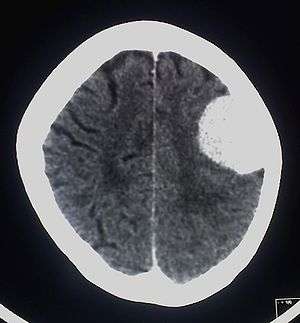

A meningioma that previously had been operated on, with surrounding edema

Meningiomas are visualized readily with contrast CT, MRI with gadolinium,[14] and arteriography, all attributed to the fact that meningiomas are extra-axial and vascularized. CSF protein usually is elevated if lumbar puncture is attempted.